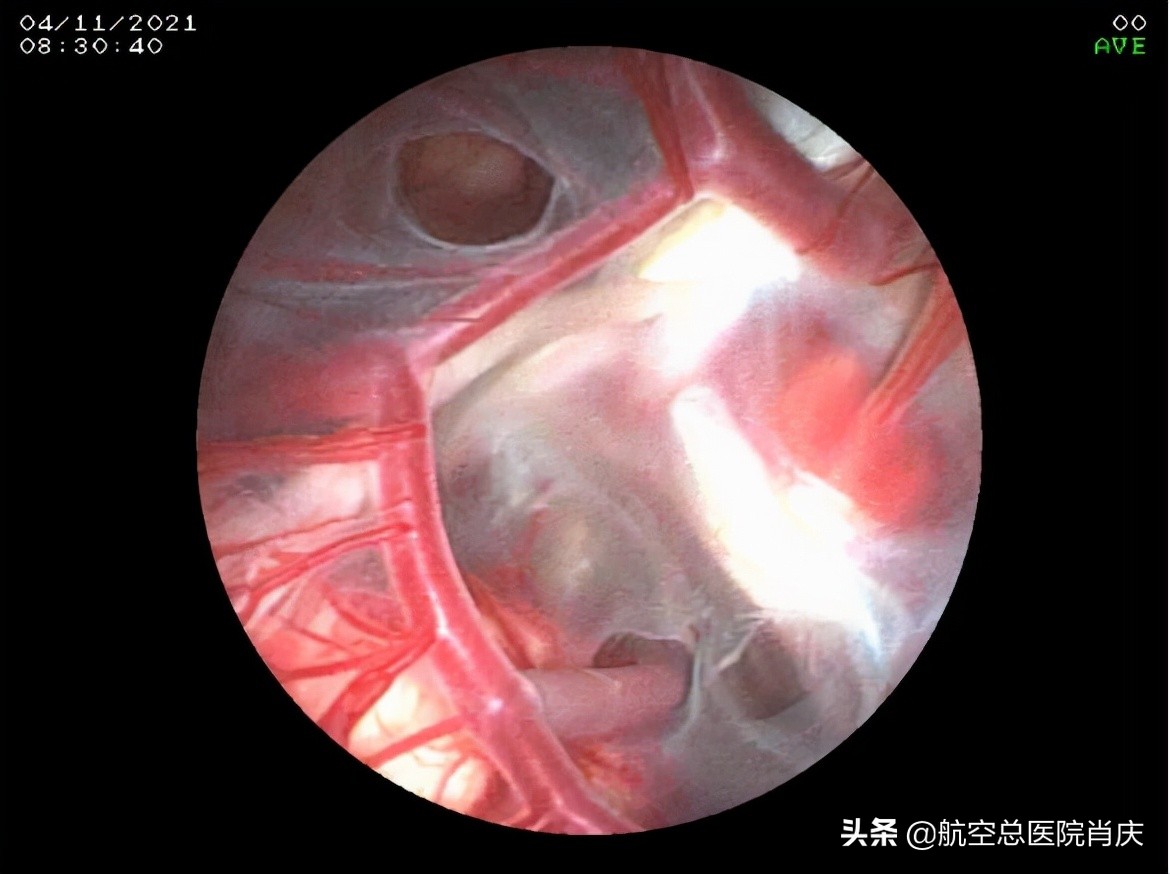

(内镜下所见鞍上池囊肿)

(鞍上池囊肿顶壁造瘘后经瘘口所见囊肿底壁及颅底动脉环)